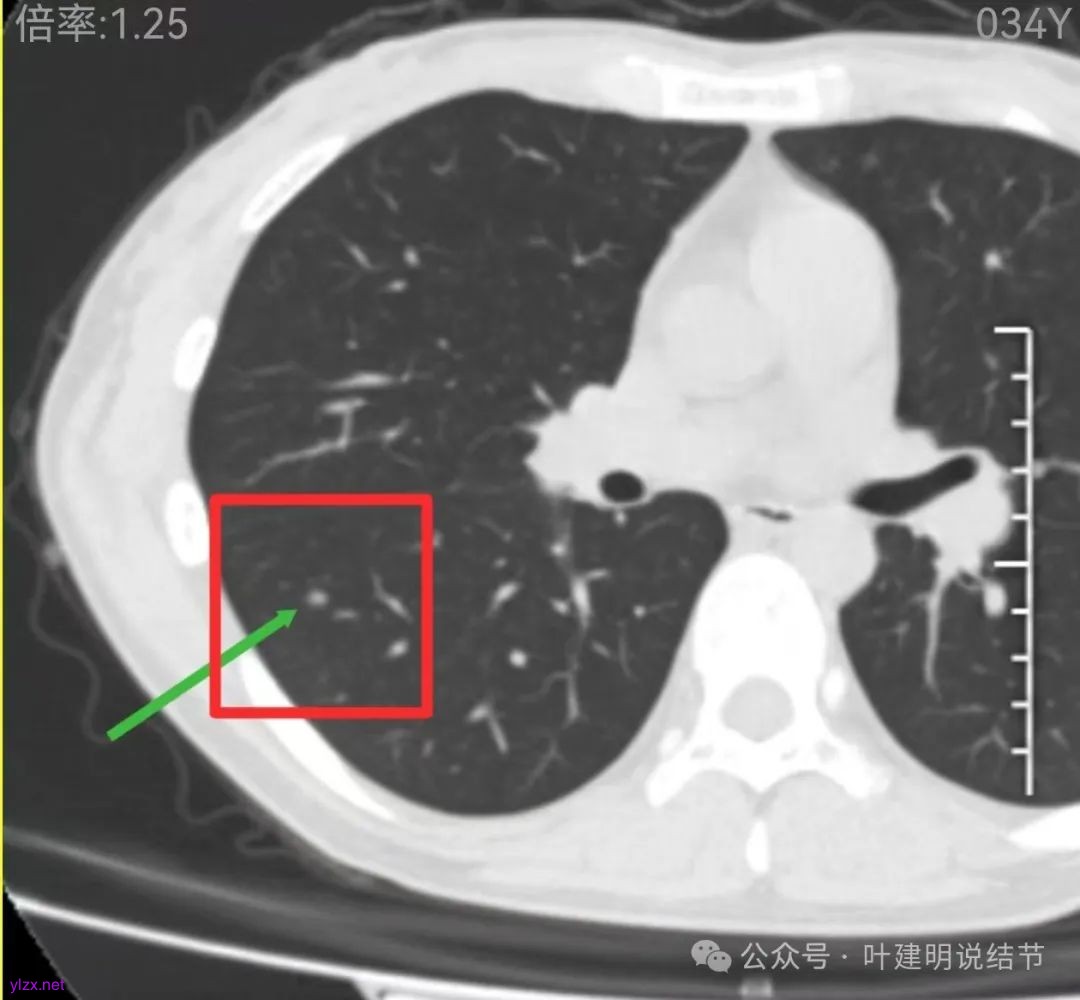

再看2022年9月的影像:

右下当时是很淡的,也显偏模糊的磨玻璃影。

边缘区也瘤肺界限稍糊,整体轮廓还行。有进展的是不是就是淡磨那处?

两肺多发结节,左侧黄色标注的考虑是肺泡上皮增生可能性大;蓝色的考虑肺泡上皮增生或者少许慢性炎可能性大;右侧红色宽起来并带有红色箭头的这处是主病灶,偏混合密度,整体轮廓较为清楚,边缘显得毛糙,从2024年12月份的来看,要考虑是肿瘤范畴,原位癌或者微浸润性腺癌可能性较大,也不能完全排除不典型增生。但是在2022年的时候,这个病灶的边上也有一个实性的微小结节,如果只看2022年的,这么小的实性结节,又比较圆,表面也显得较为光滑,是要考虑良性的,当然太小了需要动态观察。回头再重新来看2024年底的,发现绿色箭头所指的这个微小实性的较2022年几乎没有变,去仔细寻找2022年的,发现当时在实性结节旁边也有密度很淡的一点磨玻璃影(也可能真的就是一处,只是扫描不够薄,密度的变化有些突兀而已),而到了2024年12月份,实性微小这处没有明显变化,但是原来很淡的磨玻璃变成了混合磨玻璃,范围也明显扩大。所以总体来看右肺下叶这处是考虑恶性的,而且从磨玻璃结节角度来讲,还是生长比较快的,就是说还是有一定风险的。加上左侧还有两处也是磨玻璃持续存在,虽然边缘轮廓显模糊一点,但多年以后也可能仍然要变成原位癌或者微浸润性腺癌之类的东西。通盘考虑以后,我倾向于右侧近期单孔胸腔镜下微创局部切除,左侧随访观察,等到有进展并风险增加再来考虑处理。意见供参考!